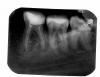

zolotajka Опубликовано 15 июня, 2009 Поделиться Опубликовано 15 июня, 2009 Зуб депульпирован несколько лет назад и запломбирован. Время от времени побаливал при нажатии на него, но вскоре боль проходила. Последние два зуб дня начал пульсировать, сегодня сделала рентген - обнаружили гранулему. Посоветуйте, пожалуйста, варианты оптимального лечения. Ссылка на комментарий

Снежана Опубликовано 15 июня, 2009 Поделиться Опубликовано 15 июня, 2009 2. Коронорадикулярная сепарация с ампутацией проблемного корня (то есть рассечение зуба вдоль на две половины, и удаление проблемного корня).ну там вообще то на обоих корнях проблемы Ссылка на комментарий

Bier Опубликовано 16 июня, 2009 Поделиться Опубликовано 16 июня, 2009 что-то там явно есть. Если коронка зуба не интактная - значит точно есть. про вкладку и коронку и читайте на stom.ru "записки доброго стоматолога" Ссылка на комментарий

Dr. Stom Опубликовано 16 июня, 2009 Поделиться Опубликовано 16 июня, 2009 можно и неудалять в рот смотреть надо)))судя по снимку с 6 скорей всего все будет ОК Ссылка на комментарий